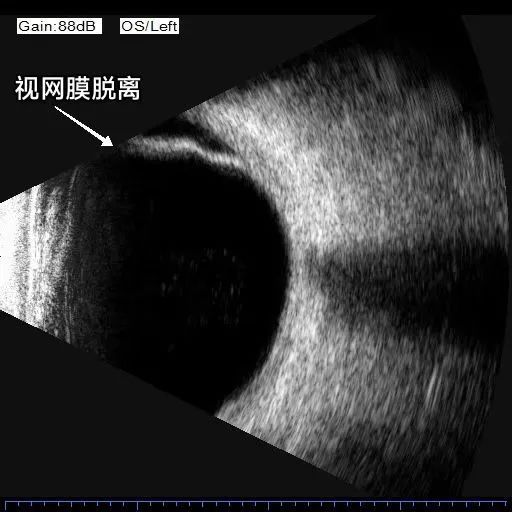

眼部B超檢查

儀器:B型超聲診斷儀

功能:排查眼內、眶內病變,如視網膜脫離、眼內及眼眶腫瘤等。

結果示例